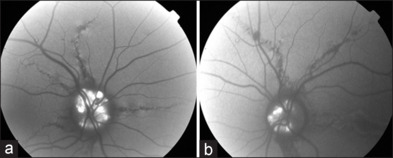

Bilateral angioid streaks in a young patient with pseudoxanthoma elasticum.

一名年轻假黄瘤患者的双侧血管样条纹。